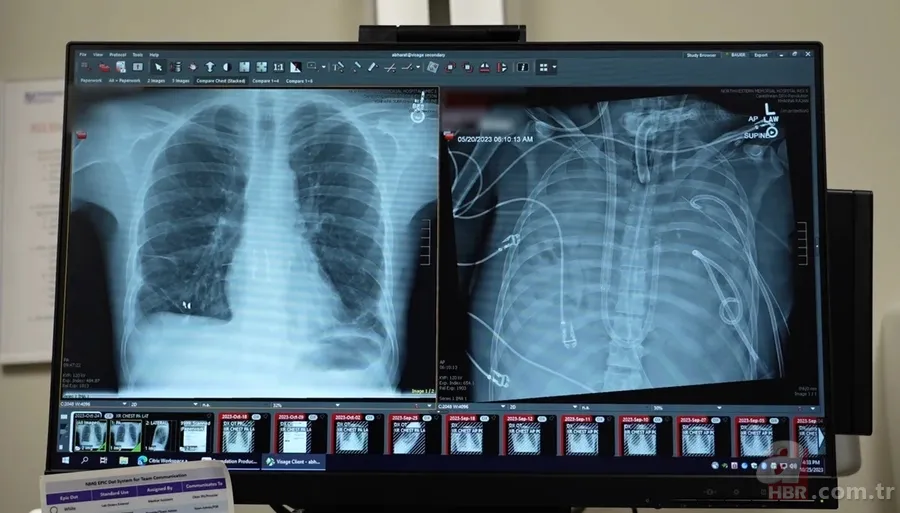

Cerrahlar, kanı vücut dışında oksijenlendiren gelişmiş bir yapay dolaşım sistemi kurdu. Bu sistem, iki gün boyunca kandaki karbondioksiti temizledi ve oksijen sağladı. Aynı zamanda kalbin üzerindeki basıncı dengeledi. Böylece diğer organların toparlanması için zaman kazanıldı.

Uygun donör akciğerler bulunduğunda hastanın genel durumu nakli kaldırabilecek seviyeye gelmişti. Operasyon başarıyla tamamlandı. Çıkarılan eski akciğerler incelendiğinde dokunun tamamen geri dönülemez şekilde hasar gördüğü doğrulandı.